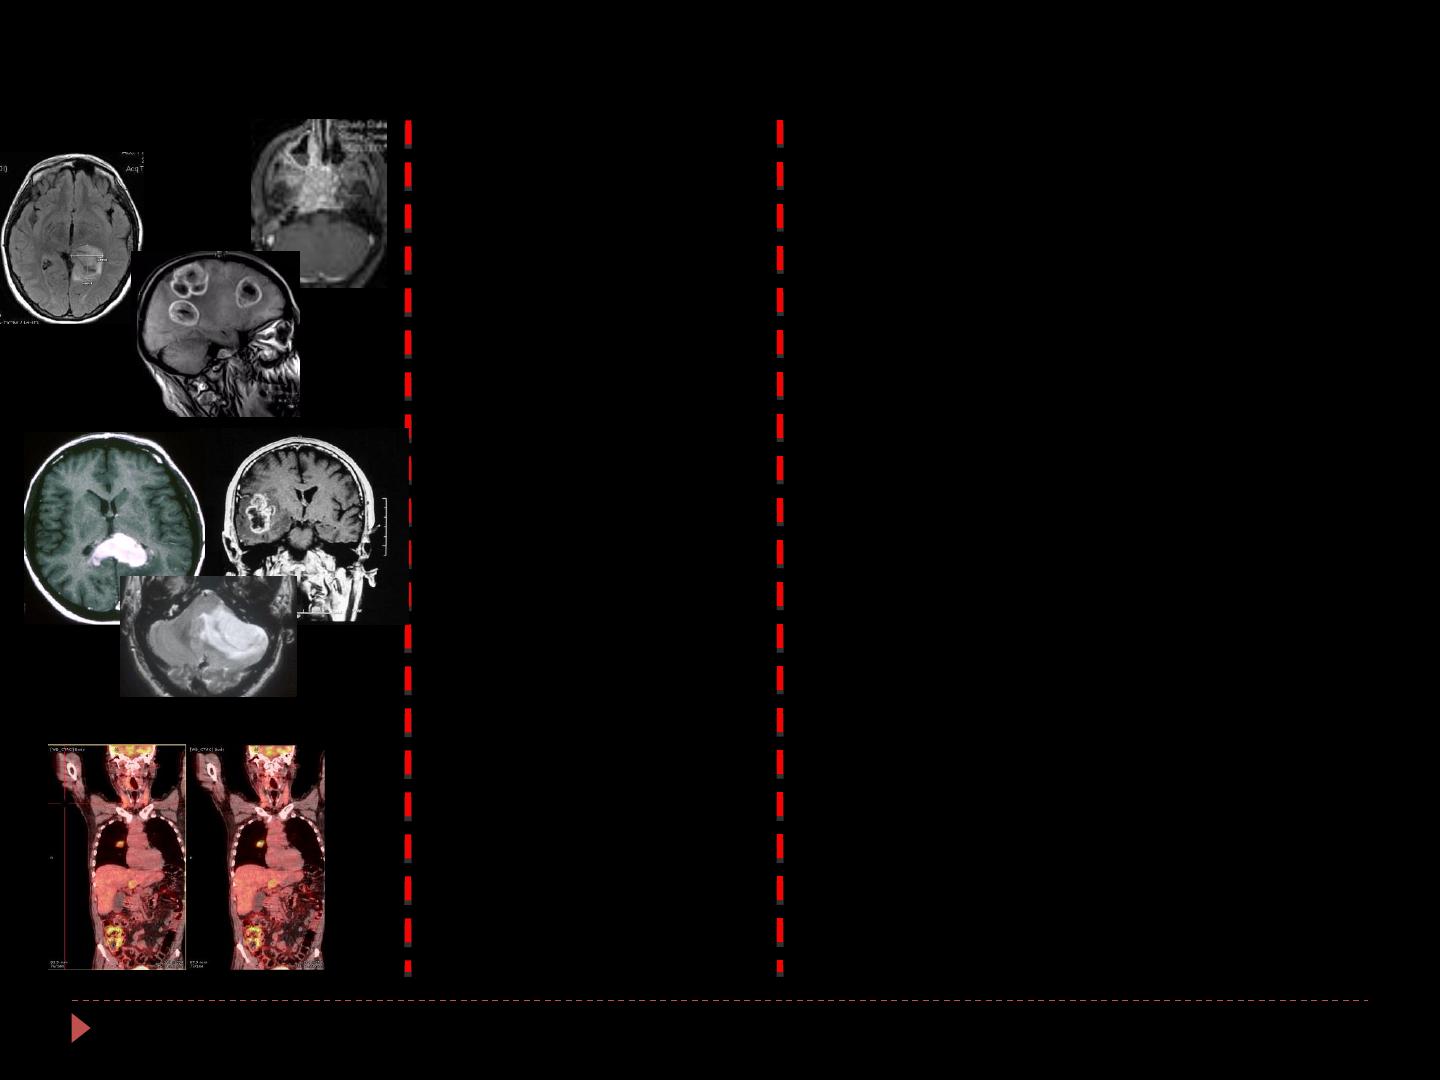

Situations cliniques Agent toxique Complications

Rayons X, γ, Protons

Rayons X

+

Polychimiothérapie

Chimiothérapies

Leucopathie

Radionécroses précoces

SMART

Tbles cognitifs transitoires

Radionécrose focale

Prises de contraste

Encéphalopathie réversible postérieure

Chemobrain?